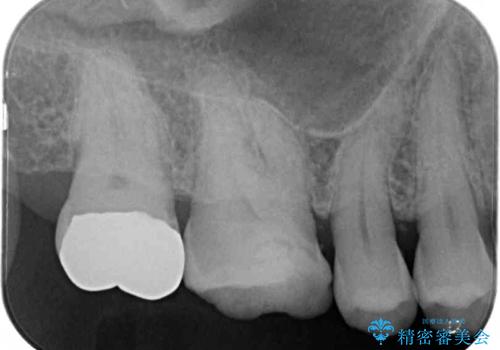

- 銀歯が外れてしまったとのことで来院された患者様です。

上顎奥の粘膜に近い部分で、外れた銀歯の下には大きく虫歯が広がっていました。

虫歯をしっかりと取り除き、ゴールドインレーにて修復することとしました。